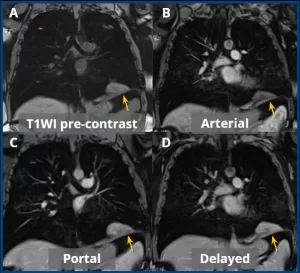

Pre-contrast (A) and post-contrast T1-weighted sequences in the arterial (B), portal venous (C), and delayed (D) phases, all with fat suppression, demonstrate slow and progressive enhancement after contrast administration (yellow arrows).